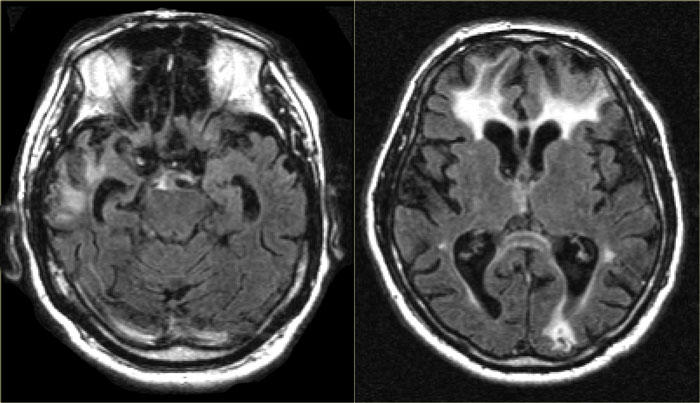

The images show bilateral thalamic infarctions - lesions often associated with cognitive dysfunction.

Transverse FLAIR images in two different patients. Transverse FLAIR images in two different patients.

Study the images of two different patients.

Then continue reading.

The image on the far left shows an infarct in the vascular territory of the Posterior Cerebral Artery (PCA), with involvement of the inferior medial temporal lobe which includes the hippocampus.

This is a strategic infarction, since it is in the dominant hemisphere, it will result in cognitive dysfunction.

The image next to it is a transverse FLAIR image showing another infarct in the PCA-territory, with involvement of the temporo-occipital association area.

This is another example of a strategic infarction that can result in cognitive dysfunction.